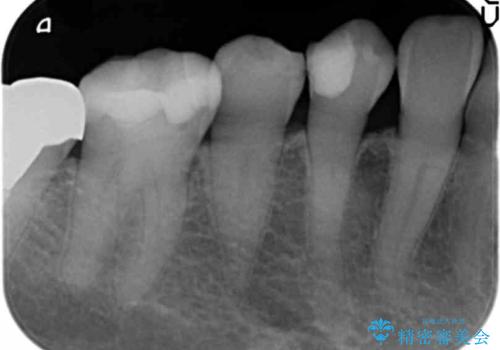

- 歯が欠けて舌が引っかかることを主訴に来院された患者様です。

精査したところ、右下小臼歯(右下4)が欠けていました。

古いレジンを取り除いてしっかり治療したいという患者様のご希望により、セラミックインレーによる修復を行いました。

インレーの種類:e-max press セラミックインレー